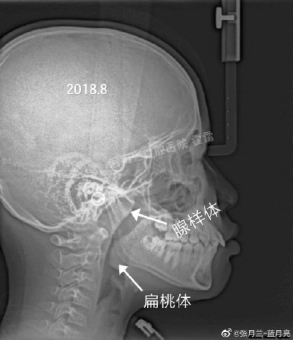

之前,郑州大学口腔医学院正畸教研室的张主任在微博发了一组图片:

一名11岁的男孩,因为“嘴巴往外突出”,想要做矫正。

经过医生询问,发现男孩有晚上“张口睡觉”的习惯,进一步拍片检查后发现:男孩有严重的鼻腔气道阻塞。

而这,才是造成男孩“嘴突”的真正原因。

在医生的建议下,男孩做了扁桃体和腺样体切除手术。一年后再复查,孩子的“嘴突”现象,慢慢不见了。

“腺样体”肥大

还会影响孩子学习